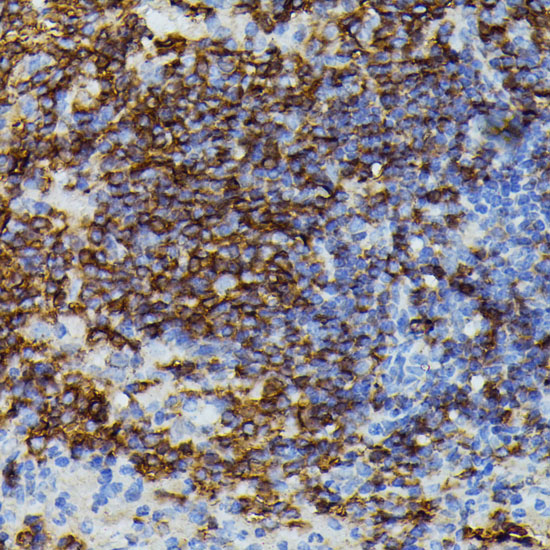

DescriptionAPOC3 Polyclonal Antibody. Unconjugated. Raised in: Rabbit.

ImmunogenA synthetic peptide corresponding to a sequence within amino acids 1-99 of human APOC3 (NP_000031.1)

ApplicationWB, IHC, IF